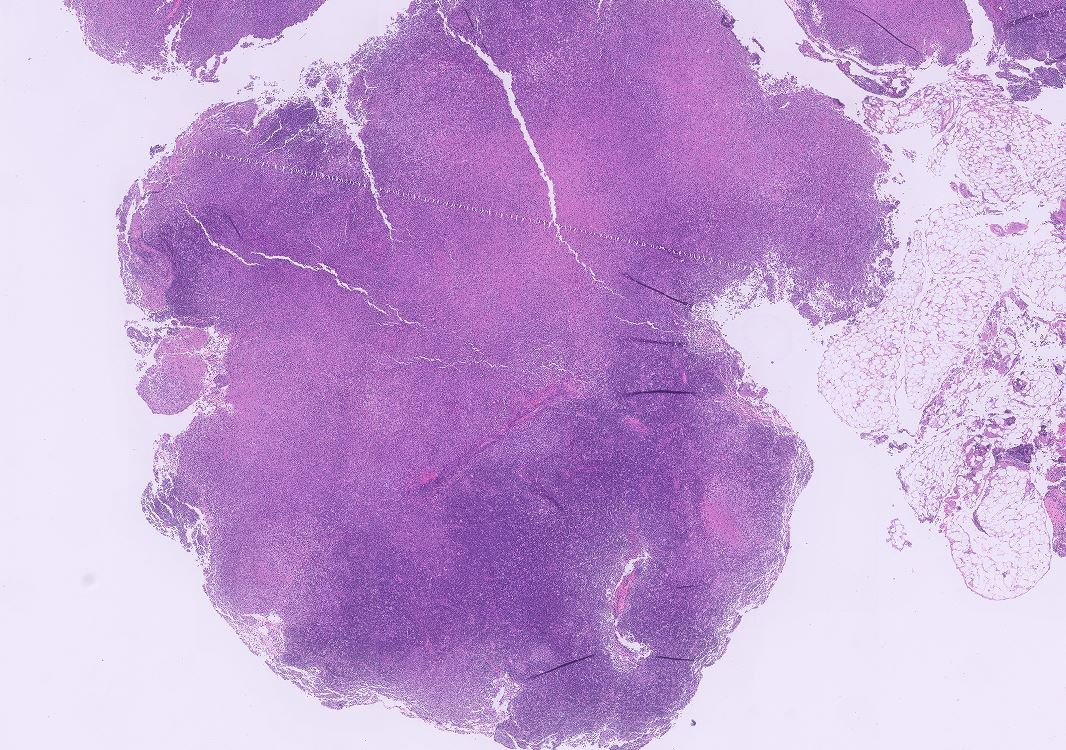

Relapsed classic Hodgkin lymphoma (CHL) with brighter PAX5 expression then typically accepted for CHL, and associated new emerging follicular lymphoma in the same lymph node biopsy (bottom right of Figure 1) #hemepath #lymsm #pathX #MedX #SoMe #Surgpath #MedTwitter #Pathtwitter

SibaElHussein's tweet image. Relapsed classic Hodgkin lymphoma (CHL) with brighter PAX5 expression then typically accepted for CHL, and associated new emerging follicular lymphoma in the same lymph node biopsy (bottom right of Figure 1) #hemepath #lymsm #pathX #MedX #SoMe #Surgpath #MedTwitter #Pathtwitter